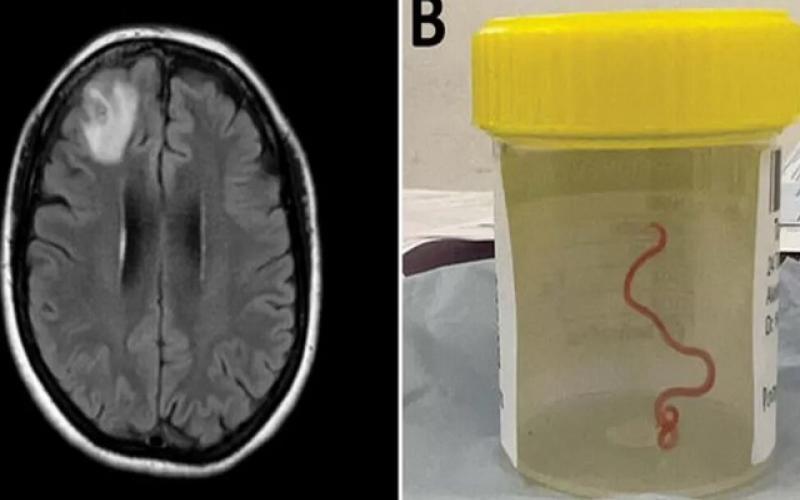

پزشکان برای اولین بار در جهان کرم انگلی هشت سانتی‌متری را از مغز یک زن خارج کردند.

به گزارش سیتنا، وقتی زن ۶۴ ساله استرالیایی برای جراحی مغز به بیمارستان فرستاده شد، جراح مغز و اعصاب، انتظار نداشت که یک کرم گرد انگلی زنده ۸ سانتی متری را از جمجمه او بیرون بکشد.

بر اساس بیانیه مطبوعاتی دانشگاه ملی استرالیا و بیمارستان کانبا، آزمایشات مولکولی تأیید کرد که این کرم Ophidascaris robertsi است، یک کرم گرد که معمولاً در مار پیتون یافت می شود.

سنانایاک که همچنین استاد دانشگاه ملی استرالیا است، می‌گوید: «طبق اطلاعات ما، این اولین موردی است که مغز هر گونه پستانداری، انسان یا غیر آن را درگیر می‌کند».